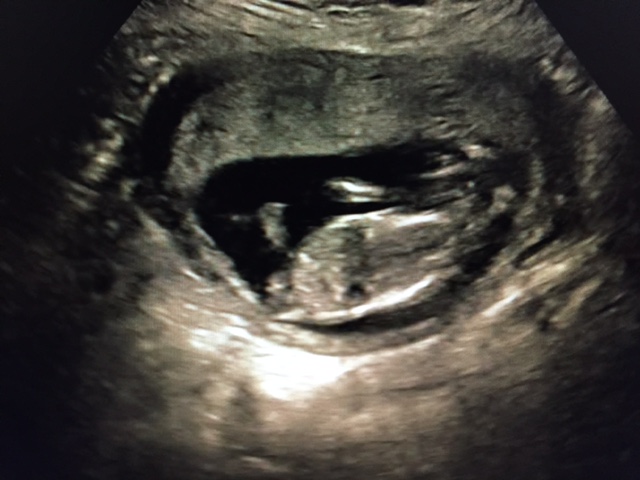

I don't know anything about the nub theory, and I don't even know if you can see a nub in these pictures :-)

Maybe boy but I cant see anything super clear

Oh wow. Well, I would trust your blood test.lol! The first pic just looks like the nub is pointing straight up! :)

Top pic does show a stacked boy nub but possibly the image doesn't capture whole nub. Congrats on your girl :-)

I think we just see a part of the leg, I don't think it's a nub we see...

The thing in the first pic is not a nub, it's cord.

I agree with atomic, I think it's a cord, not a nub. Even though it is easy to think it is a nub, it's actually too high up.